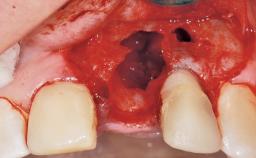

Late Flapless Placement of an Implant in a Maxillary Left Central Incisor Site

A 39-year-old male patient presented with a chief complaint of discomfort and gingival discoloration around his maxillary left central incisor. He was in good general health and was a non-smoker. His past dental history was significant because of the traumatic fracture of tooth 21 in a sporting accident at age 13. Initial dental treatment included endodontic therapy and a full-coverage restoration. The patient became symptomatic 5 years later, when structural failure of the tooth resulted in the dislodgment of the crown. Endodontic retreatment, apical surgery, and post-and-core restoration were performed.

Soft Tissue Grafting Simultaneous

Soft Tissue Anatomy Intact Defective